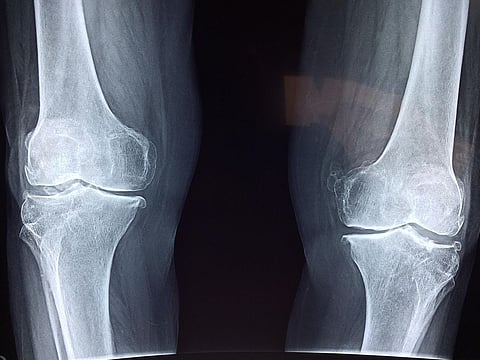

Representational image. Pixabay

Joint pain can affect many parts of the body including hands, hips, knees, fingers, back and neck. This makes movements that many of us take for granted, like having sex, holding hands or cuddling incredibly painful.